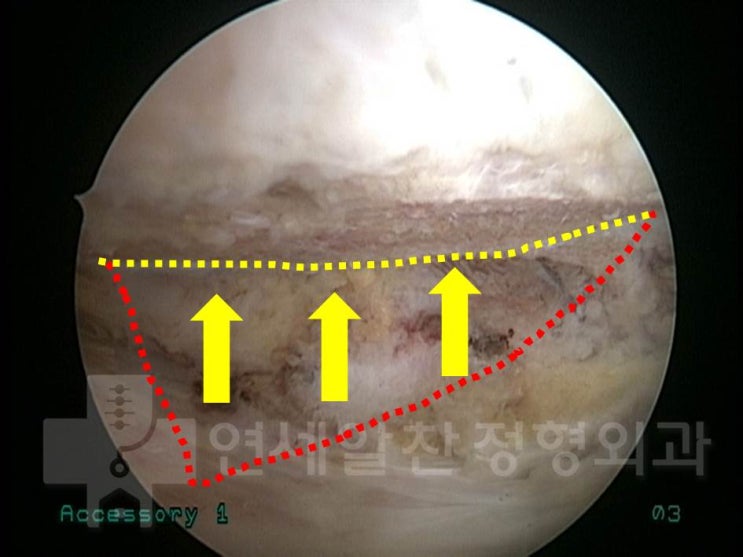

Arthroscopic Repair and Acromioplasty for Bursal-Side Partial Tear of the Supraspinatus

Dr. Dongkyu Lee